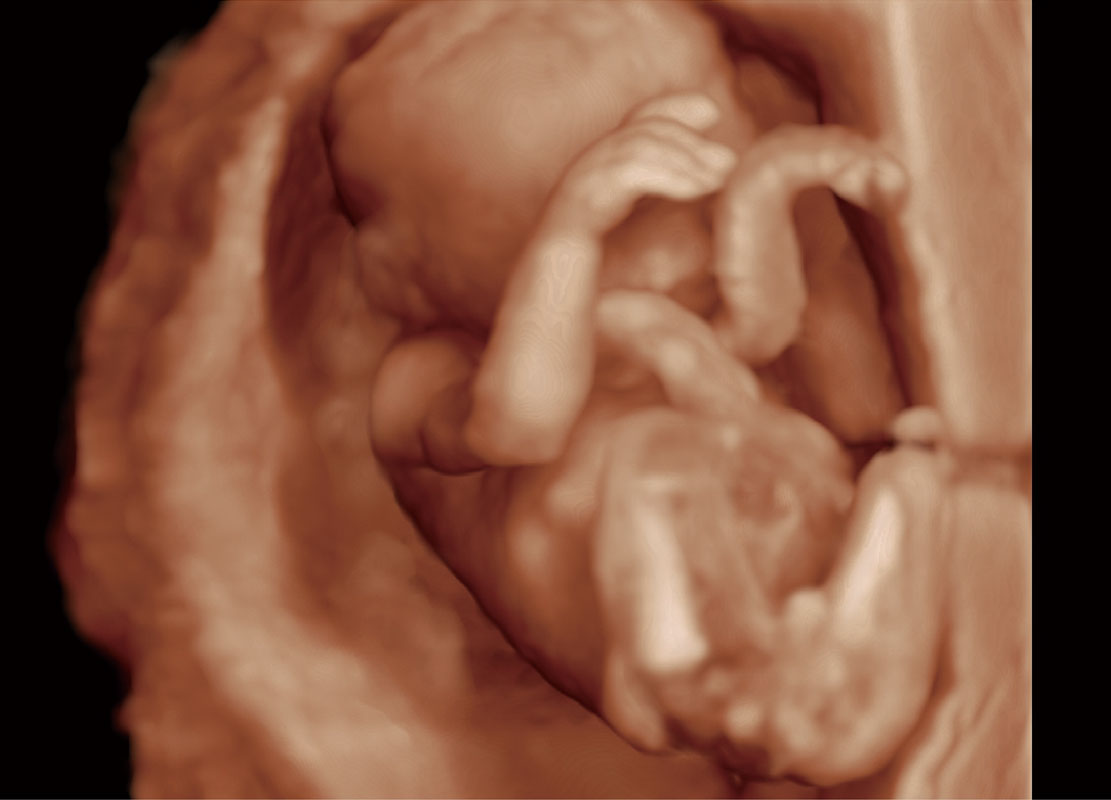

高分辨率容积成像-早孕胎儿